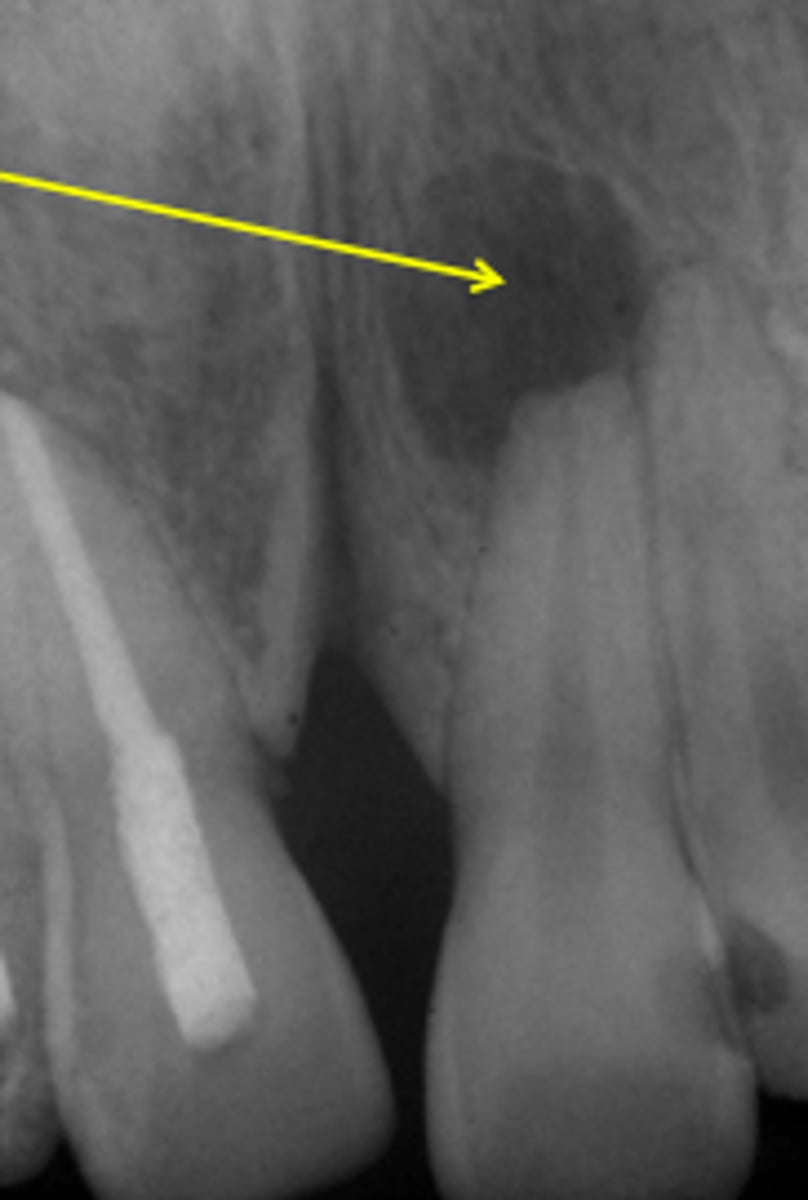

Radiographic features of chronic osteomyelitis

radiolucency

mixed radiolucent-radiopaque

sequestration, fistula, fracture